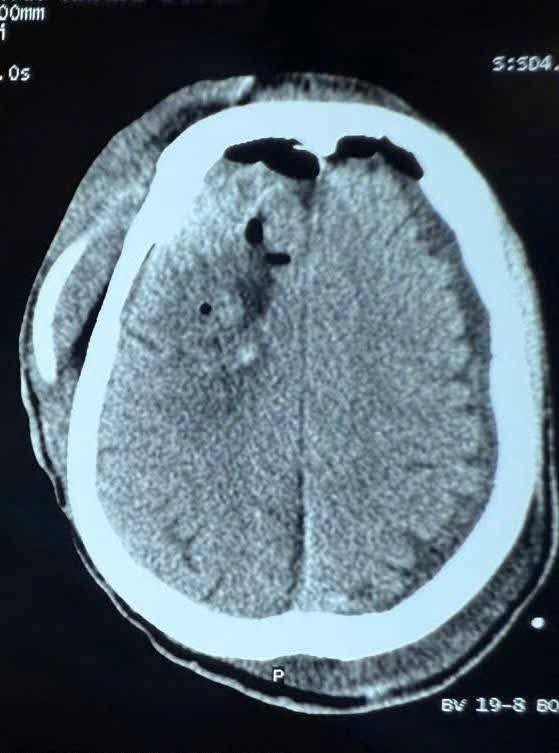

chan-thuong-1.jpg

Hình ảnh chấn thương não sau cơn động kinh - Ảnh BSCC